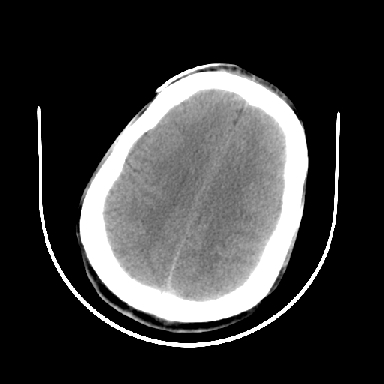

以下是引用dyqct在2007-4-9 11:18:00的发言:[br]左额颞顶叶、基底节区呈大片低密度区,累及皮质,中度占位效应,同侧侧脑室旁见小片状高密度区,边界清楚。中线结构向右弧形移位。右侧侧脑室略扩张。[br]考虑:1、左侧额颞顶叶、基底节区缺血性脑梗塞(符合大脑中动脉供血区)伴出血。[br] 2、建议增强扫描进一步检查。

以下是引用卜一在2007-4-9 15:08:00的发言:[br][br] 左侧额颞顶叶、基底节区缺血性脑梗塞(符合大脑中动脉供血区)伴出血。原因:多考虑外伤后出血,形成血栓所致。 [br]